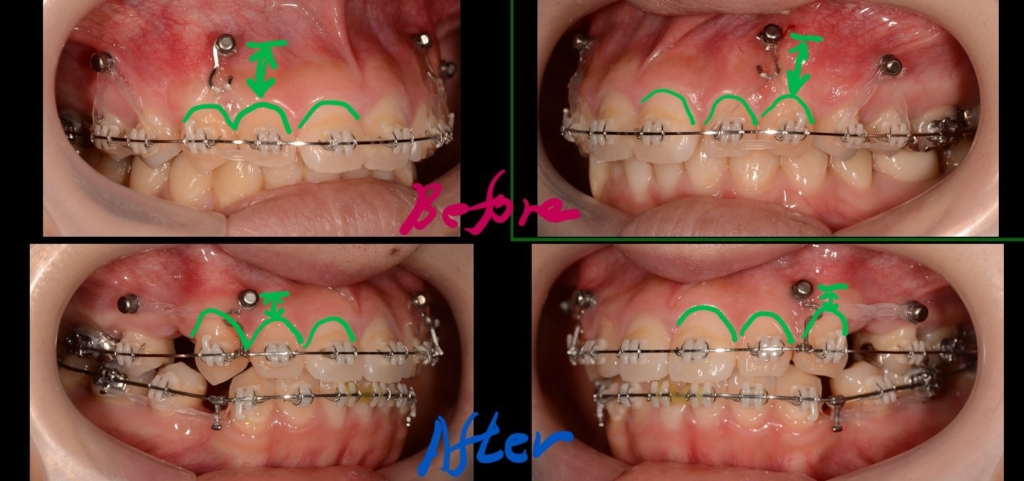

治療に伴う歯肉の変化をお見せしましょう。

上段が圧下治療開始時点、下段が圧下治療終了後 になります。

アンカースクリューは動きませんから、上記の写真を見れば、圧下治療に伴い前歯が周りの歯肉ごと押し込まれて歯肉の見え方が狭くなったことが一目瞭然で分かると思います。

便宜上、「圧下」という言葉を使いますが、「持ち上げる」という言葉の方が実態を表しているかもしれません。